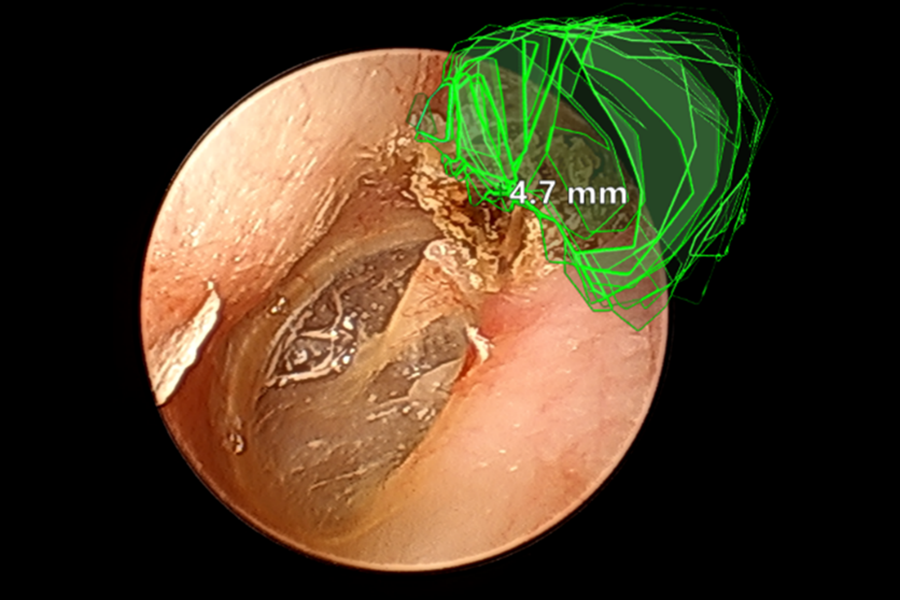

鼓室形成術はほぼ全例が内視鏡手術で完遂しており、耳の後ろを大きく切る必要はありません。真珠腫が大きい場合であっても、約2㎝の皮膚切開から拡張現実型(AR)ナビゲーションシステムを用いて安全に真珠腫摘出を行う方法、画像誘導経皮的内視鏡下耳科手術(IGPEES)(文献1)を開発、実用化しています。

(文献1)Masaya Uchida, et al. Efficacy of Image-Guided Percutaneous Endoscopic Ear Surgery: A Novel Augmented Reality-Assisted Minimally Invasive Surgery. Otology & neurotology 46(5): 532-538, 2025